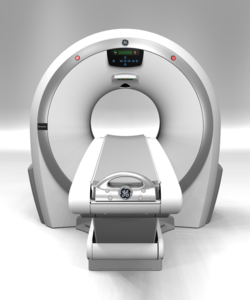

TAC

Grazie alla collaborazione con GE scil ti offre tecnologie all’avanguardia anche nel campo della Tomografia Computerizzata (TC), che ridefinisce gli standard finora raggiunti. Revolution ACT consente nuove opportunità diagnostiche e un miglioramento delle prestazioni a costi contenuti.

L’estrema compattezza la rende, inoltre, una soluzione ideale per ogni Clinica e il più prezioso

strumento di imaging diagnostico per offrire una gamma sempre più completa e avanzata di cure.

Che la rivoluzione abbia inizio. Scopri di più.